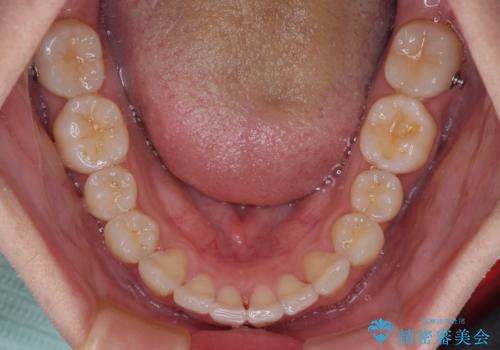

前歯のデコボコをインビザラインで綺麗に改善

- 上下前歯のデコボコとクロスバイトを気にして来院された患者様です。

インビザラインを用い、IPR(歯と歯の間を削る)と歯列全体を拡大させることで、歯並びを整えていくこととしました。

毎日22時間の装着時間を徹底してくださったのですが、左右ともに臼歯が咬合しなくなるという、インビザライン独特の症状が強く長く続いてしまい、終了するまでに長期間を要してしまいました。